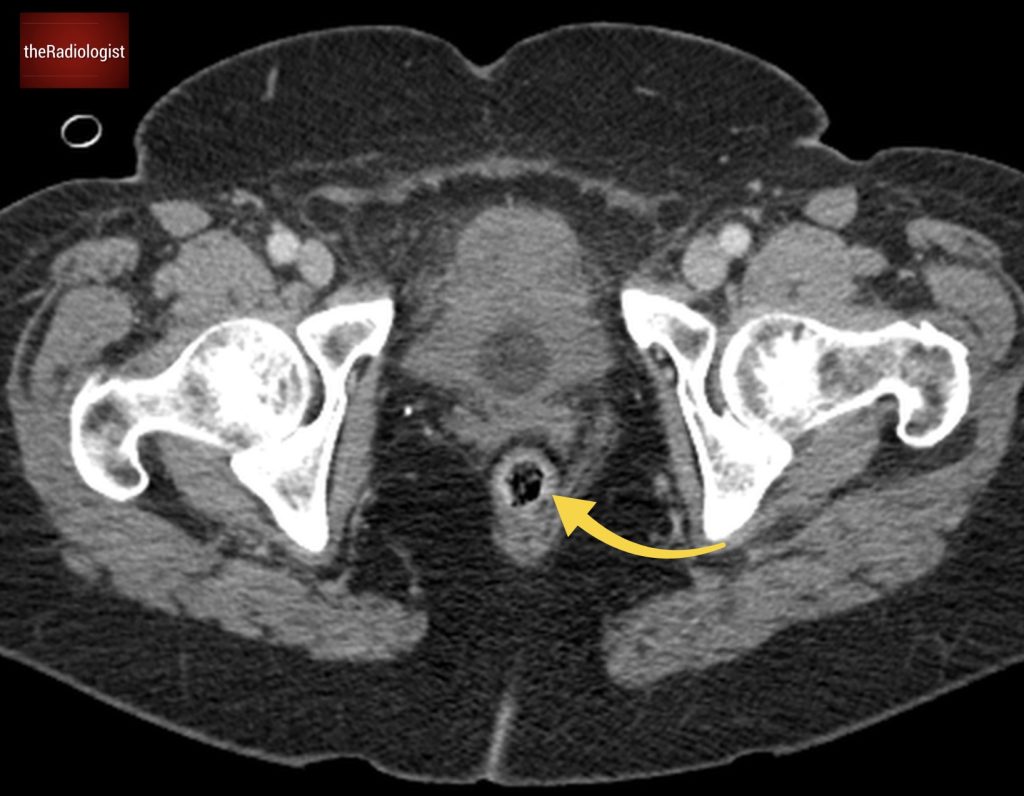

Also as we scroll down we can see there is fat stranding surrounding the psoas muscle extending into the pelvis.

There is fat stranding surrounding the psoas extending into the pelvis.